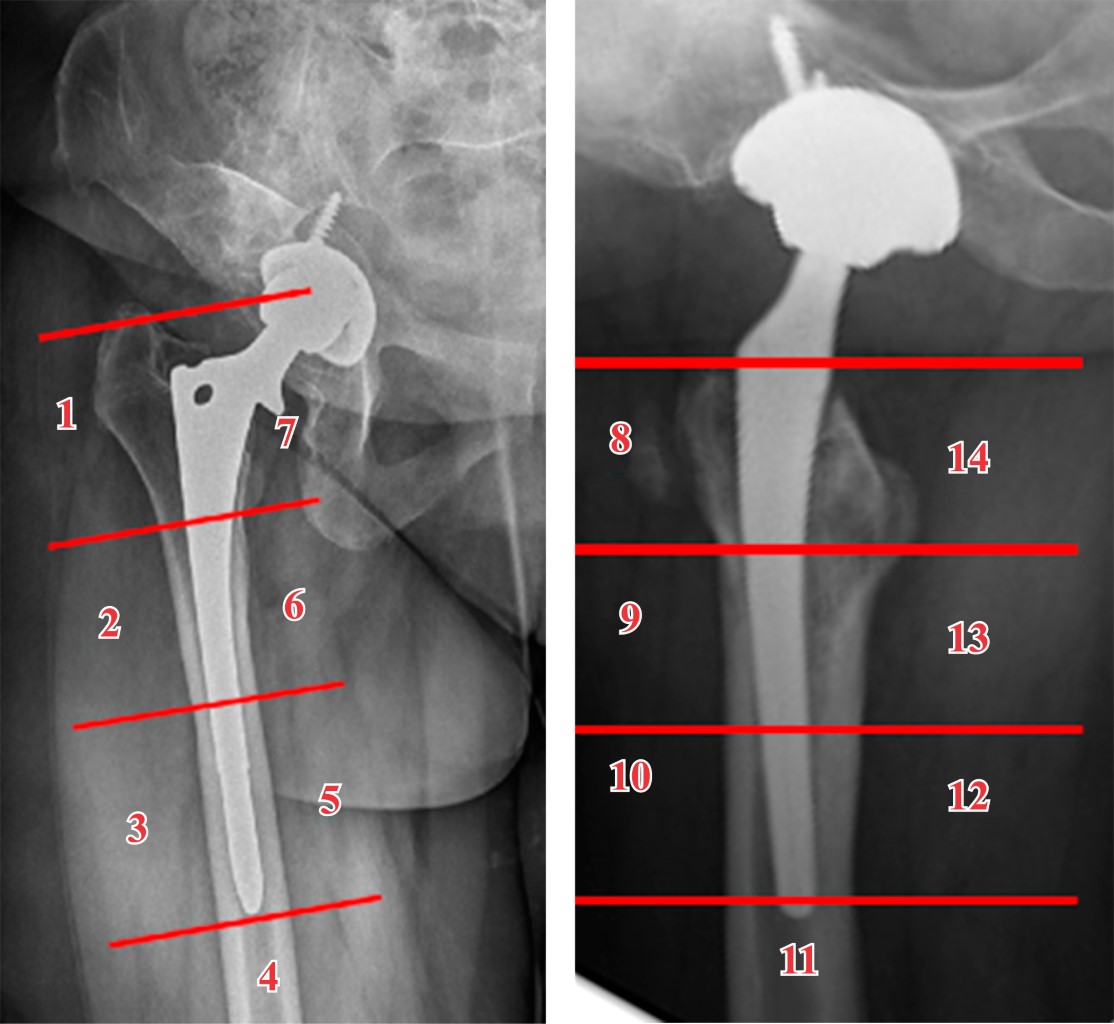

Minimizing risk: evaluation of the relationship between femoral stem loosening and the risk of presenting with peri-prosthetic hip fracture

Introduction: evaluation of predictors of periprosthetic fracture in loosened femoral stems. Material and methods: retrospective case-control study comparing aseptic loosened stems in two groups: cases: patients who experienced periprosthetic femoral fracture before replacement could be performed (n = 9). Controls: experienced prosthetic replacement without fracture (n = 19). Results: pain intensity (VAS) was the most important aspect (p = 0.01), predominating in the controls. The simple radiological parameters did not show statistically significant findings predictive of peri-prosthetic fracture (number of Gruen zones, sum of them in mm, stress shielding, pedestal, polyethylene wear, stem subsidence). The role of complementary tests (CT and scintigraphy) for the definitive diagnosis of loosening was relevant, but not significant. The type of implant showed no differences. Overall implant survival was higher in cases than in controls (p = 0.016). This difference continues when comparing each loosened stem until fracture or replacement (p = 0.024). Conclusion: the main factor protecting against fracture is the replacement of a stem with clinical and radiological diagnosis of loosening. Adequate follow-up of the patient plays a determining role in this, especially when considering the greater intensity of pain in the controls, which used to guide surgeons to perform replacements before the fracture occurred. This is reinforced if we take into account that up to one third of the cases did not have regular check-ups, and therefore did not have the opportunity for replacement prior to the fracture. The role of complementary tests (CT and scintigraphy) is also very important, taking into account the low diagnostic yield obtained from simple X-rays.

Figure 1